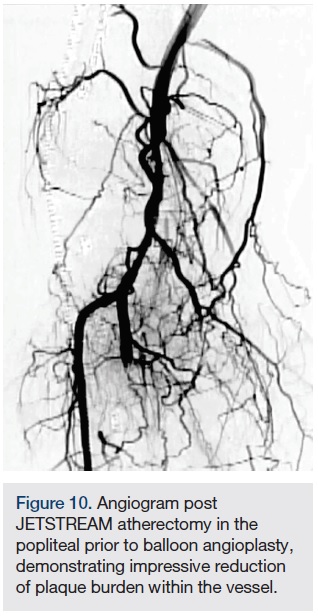

Atherectomy with JETSTREAM. Atherectomy was performed in two stages. During the first stage, we had wire access from the popliteal to the peroneal artery. Before crossing from the posterior tibial, we wanted to treat the popliteal/peroneal segment. A 2.4 mm/3.4 mm JETSTREAM atherectomy device was advanced into the popliteal and activated. The device must be activated with the blades down. A pilot channel will remove some of the plaque. The device is advanced at a rate of no more than 1 mm per second. The operator will need to listen to the pitch of the device. A depressed pitch suggests that the device rotation has slowed down, and the operator should then carefully pull the device back and re-advance. The operator must not allow the aspirational capabilities of the device to be overwhelmed. After successful atherectomy “blades-down,” a “blades-up” run was then performed with the JETSTREAM device (Figure 7). During the second stage of atherectomy, the peroneal and posterior tibial arteries required further therapy. For this stage, we obtained posterior tibial access, crossed the posterior tibial CTO, and snared the posterior tibial wire. We proceeded with the use of a 1.85 mm JETSTREAM device. The tibial device has the rotational capabilities without the “blades-up” feature, and also features active aspiration, like the larger JETSTREAM devices. We were able to atherectomize the posterior tibial and peroneal arteries (Figure 8). Angiographic images post atherectomy demonstrate significant plaque reduction. After atherectomy, we proceeded with kissing balloon angioplasty of the popliteal/peroneal and posterior tibial arteries (Figure 9). Angiography of the popliteal artery post atherectomy showed significant improvement (Figure 10). After removal of the pedal sheath, brisk flow was noted (Figure 11). The procedure was concluded with the resolution of the stenosis from the popliteal artery and restoration of flow in two tibial vessels (Figure 12).